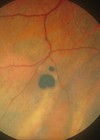

The macula

What is the macula dependant on for blood supply?

Underlying choroidal circulation